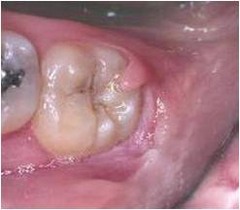

chronic hyperplastic pulpitis

-Red or pink nodule protruding from the pulp chamber or a tooth with a large open carious lesion (usually molars)